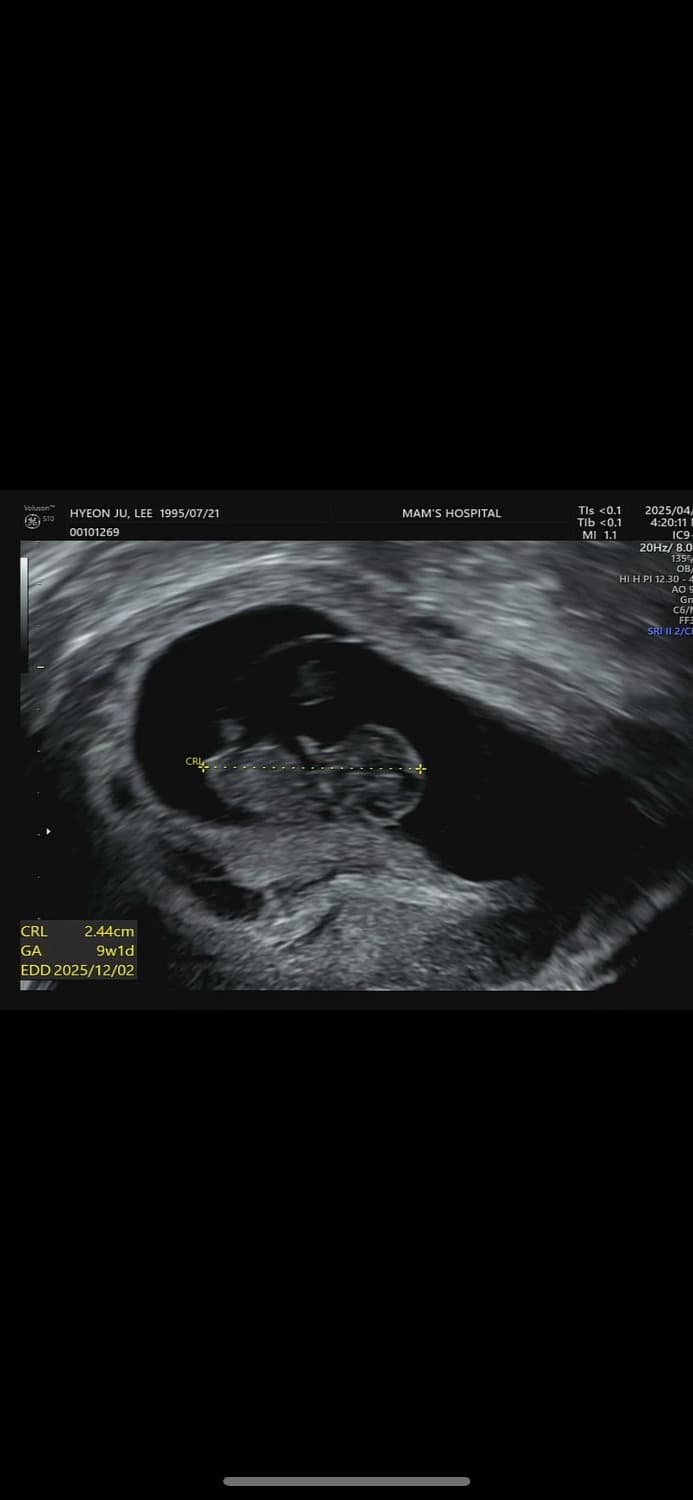

임신 9주차이구요 오늘 병원가서 질 초움파보는데 피고임있다고 유산가능성이 있다고 말씀하시더라구요 그래서 유산방지주사랑 질정 처방받아서 왔는데 어느정도로 심각한건가요? 피고임이 많은건지 확인이 될까요??